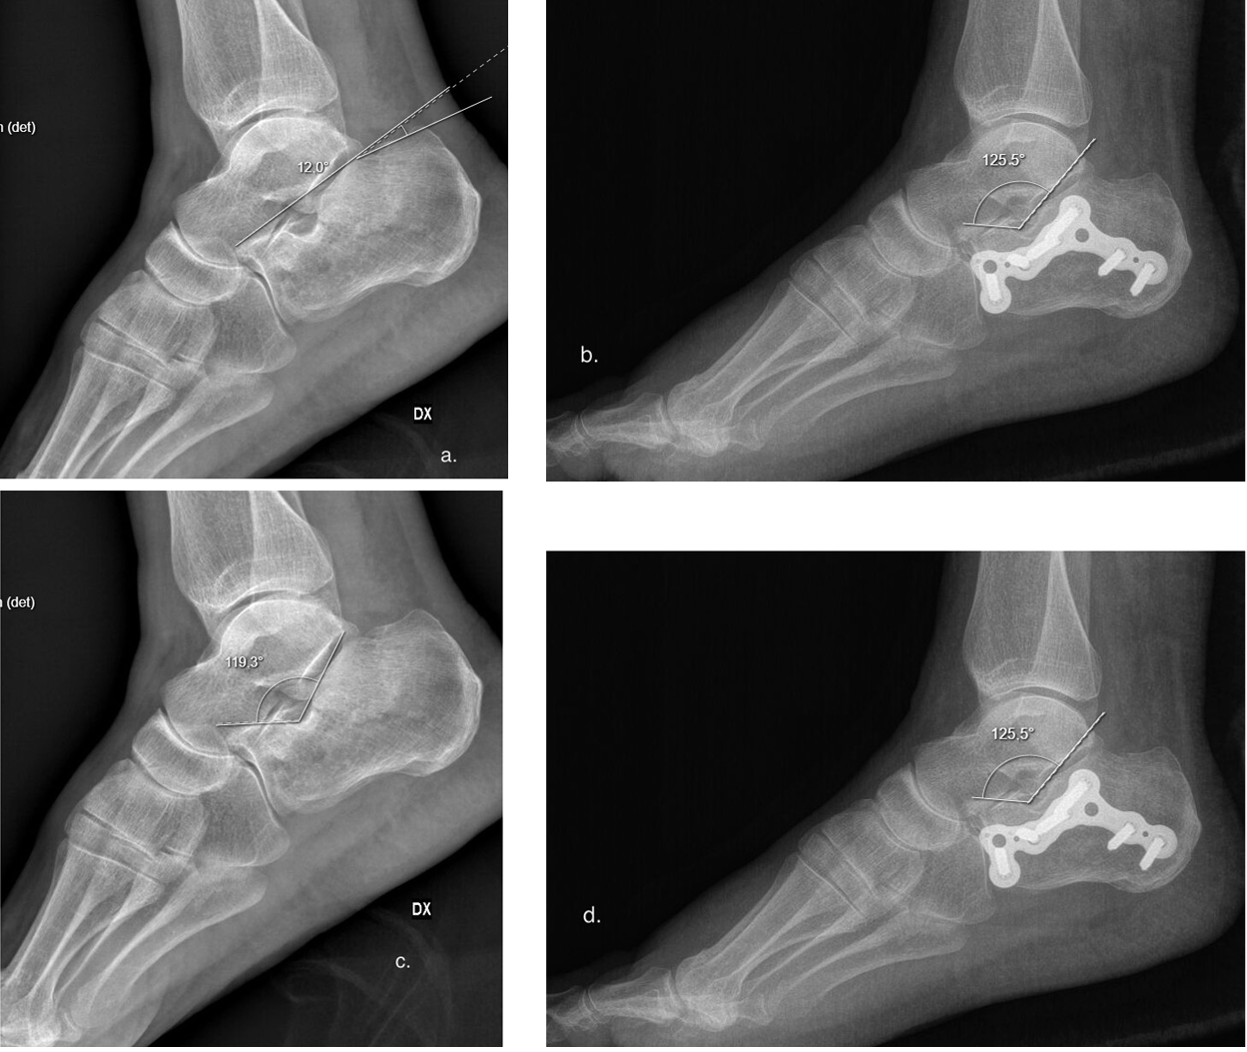

Böhler’s and Gissane’s angles16,17 were measured on the pre- and post-operative lateral radiographs (Figure 3a-d).

Figure 3. a, preoperative and (b) postoperative X-ray with Böhler’s angle measurement. c, preoperative and (d) postoperative X-ray with Gissane’s angle measurement.

The median preoperative Böhler’s angle was 14.2° (range 1°-32°) in the EF group, and 14.9° (range 9°-26°) in the LP group. Postoperative Böhler’s angles were 32.6° (range 20°-58°) and 30.8° (range 20°-49°) in the EF and LP groups, respectively, with median increases of 18.9° and 15.9° (Figure 5, Table 3). In both groups, improvement of postoperative Böhler’s angle was statistically significant (p<0.01)

The median preoperative Gissane’s angle was 130.2° (range 107°-180°) in the EF group, and 129.2° (range 104°-180°) in the LP group. Postoperative Gissane’s angles were 115.8° (range 82°-138°) and 116.9° (range 90°-130°) in the EF and LP groups, respectively (Table 3). In both groups, improvement of postoperative Böhler’s angle was statistically significant (p<0.01).